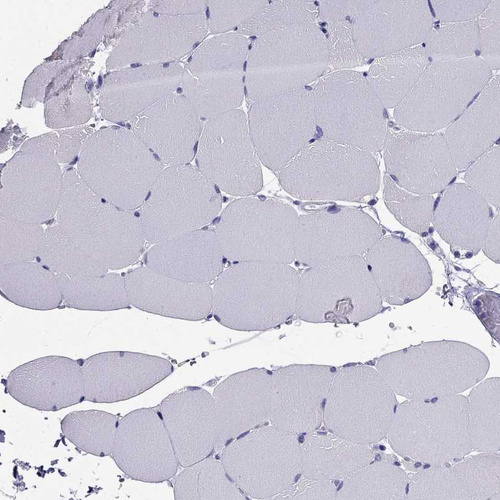

Immunohistochemistry analysis in human parathyroid gland and liver tissues using HPA048540 antibody. Corresponding PTH RNA-seq data are presented for the same tissues.